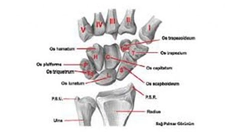

Kısa Kemikler Hangileridir